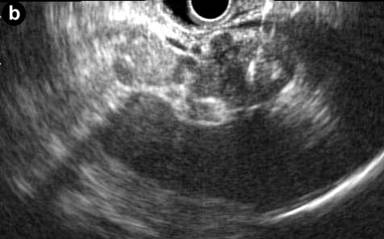

A 53-year-old man was incidentally found to have a cystic tumor in the tail of the pancreas after undergoing an abdominal ultrasound (US), which showed a 41x33 mm cystic mass in the pancreatic tail. He had no abdominal symptoms. The tumor markers, including DUPAN 2, and carbohydrate antigen 19-9, were within the normal ranges. The patient was referred to our hospital for further investigations. A contrast-enhanced CT scan (Figure 1) showed a non-enhanced cyst between the spleen and the pancreas with no solid component. Magnetic resonance cholangiopancreatography (Figure 2) revealed that the main pancreatic duct was regular and had no dilatation, and there was no communication between the cyst and the pancreatic duct. Magnetic resonance imaging (MRI) showed a lesion with a slightly high signal on a T1-weighted image; the lesion, which was well circumscribed, was in the tail of the pancreas (Figure 3). MRI on a T2-weighted image also showed the lesion with a high signal. The cystic tumor was negatively visualized on the PET image. Endoscopic ultrasound (EUS) was performed, which showed a 55x31 mm pancreatic tail lesion with a solid and cystic mixed component (Figure 4a). An endoscopic ultrasound-guided fine-needle aspiration biopsy in a trans-gastric approach of this lesion suggested a diagnosis of a benign squamous cyst (Figure 4b).

Figure 4. a. Endoscopic ultrasound was performed, which showed a 55x21 mm pancreatic tail lesion with solid and cystic mixed component. b. Endoscopic ultrasound-guided fine-needle aspiration biopsy in a transgastric approach of this lesion. |